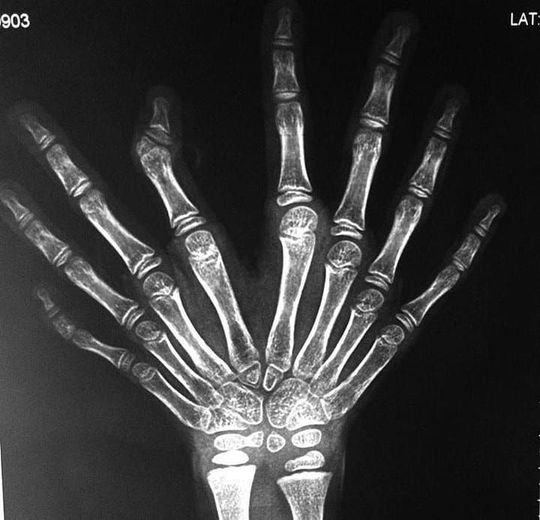

Ulnar dimelia is a rare developmental anomaly, which is characterized by absence of radius, duplication of ulna and symmetric polydactyly (seven or eight fingers and lack of thumb). Ulnar dimelia is a very rare developmental anomaly of the upper limb. There are only approximately 70 cases described in the literature. Ulnar dimelia, called also the mirror-hand, is classified to the 3rd group of congenital hand malformation, according to the classification proposed by Swanson and adopted by the American Society for Surgery of the Hand (ASSH) and the International Federation of Societies for Surgery of the Hand (IFSSH). Skeletal malformation may be followed by arterial and nervous anomalies as an absence of the radial artery, duplication of the ulnar artery, presence of abnormal arterial arches in the hand, shortening of radial nerve, duplication of ulnar nerve (sometimes with collaterals to median nerve). Tag a friend and follow us at @Medicalpedia